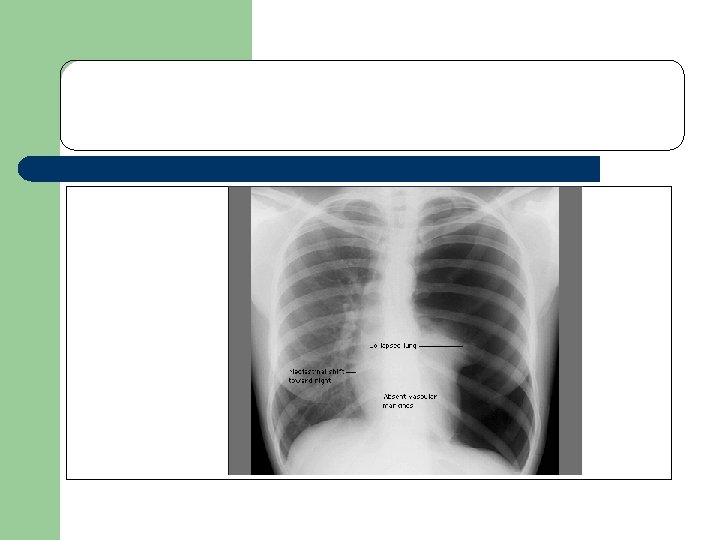

Obstructive shock l l Obstruction to the outflow due to impaired cardiac filling and excessive after load Cardiac tamponade and constrictive pericarditis impair diastolic filling of the Rt. ventricle Tension pneumothorax limit Rt. ventricular filing by obstruction of venous return Massive pulmonary embolism increase Rt. ventricular afterload

l l l Hemodynamic profile in obst. Shock Cardiac output low Afterload high Lt. Vent. filling pressure variable Pulsus paradoxicus in Tamponade Distended Jugular viens